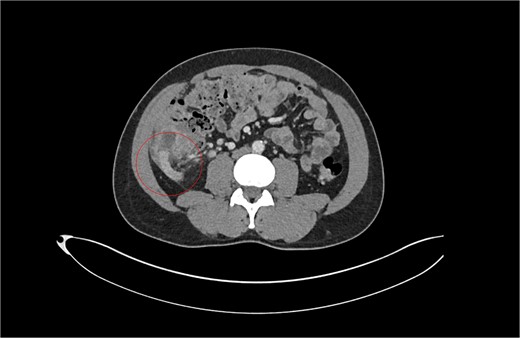

With a differential diagnosis of stump appendicitis versus nephrolithiasis, a CT KUB was done which revealed no significant findings in the appendix or kidneys—the differential was revised to mesenteric adenitis or inflammatory bowel disease. The patient was counseled to be booked for an outpatient colonoscopy. However, in view of ongoing symptoms, serial examinations and investigations revealed a rising white cell count and CRP to 264. The patient was started on intravenous (IV) antibiotics. A formal CT CAP demonstrated mural thickening and enhancement of the caecal pole and fat stranding (Fig. 2). With a diagnosis of stump appendicitis, IV antibiotics were escalated to metronidazole and piperacillin-tazobactam.

Patient B. Appendiceal stump of Patient B identified within the red circle on CT scan before the second operation.